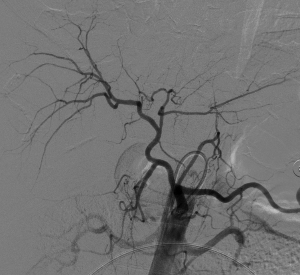

入院后,為患者給予補液,在局部麻醉下行DSA引導下經導管肝腫瘤動脈栓塞術。

手術順利,術后患者轉正重癥醫學科給予輸血、補液、止痛及康復治療。術后3天,患者復查血,肝功能正常。后續恢復良好,并在短期內出院。

肝癌破裂大出血并失血性休克患者往往病情急、危、重,如果治療不及時可能短期內死亡。未開展介入治療的醫院對此類患者只能給予輸血,補液,急診手術,在插管全麻下行開腹手術治療。但開腹手術往往切口長、手術時間長、手術創傷大,麻醉副作用大。可能術后出現肝功能衰竭,再出血,腹腔感染,切口疼痛,切口感染等并發癥。介入手術則往往較少出現這些并發癥。介入手術只需要在腹股溝穿刺一個2mm的小孔,置入導管到肝動脈,注入栓塞劑栓塞肝腫瘤的動脈,手術創傷小,止血可靠,除肝區疼痛及發熱外,較少出現其它并發癥,病人舒適度明顯提高,而且能早期進食及下地活動,恢復快,能縮短住院時間,具有療效好且微創的優點。